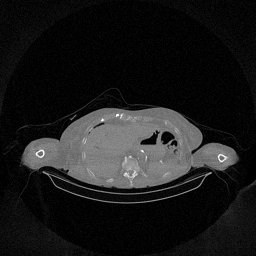

The results for simulated noisy data are shown in Fig. 2. The first and third rows display two representative slices from the test set, and the second and fourth rows present the corresponding error maps. The traditional WCE method suppresses cupping artifacts and recovers some missing anatomical structures but still shows noticeable deviations from the ground truth. Predictions from the four diffusion-based models demonstrate a markedly improved ability to restore anatomical structures. Among them, cDDPM fails to fully reconstruct the patient bed and retains residual noise in its outputs. This noise is attributable to an incomplete reverse denoising process rather than residual Poisson noise, as evidenced in our noise-free experiments (Fig. 5 in the Appendix). PatchDiffusion, diffusionGAN, and I2SB achieve similar visual quality, with I2SB producing the cleanest and most consistent reconstructions.

The experimental results on clinical head data are shown in Fig. 4. The reference images were reconstructed using the fast iterative shrinkage-thresholding algorithm (FISTA) with total variation regularization from non-truncated projection data. In the WCE reconstructions (Fig. 4(b)), severe truncation prevents accurate recovery of anatomical structures outside the FOV. Despite being trained solely on simulated data with a domain gap, all deep learning models can restore a substantial portion of the missing anatomy. Among them, the diffusion-based methods recover soft-tissue boundaries more faithfully than the conventional deep learning approach FBPConvNet, highlighting their stronger image generation capability. However, cDDPM reconstructions exhibit more noticeable noise than those from other methods, consistent with the simulated data results. The patchDiffusion model introduces artifacts within the FOV, likely due to its patch-wise processing strategy. While I2SB shares the same limitations as other diffusion models in perfectly restoring soft-tissue detail, it produces fewer residual noise patterns and fewer artifacts within the FOV boundaries. Overall, Fig. 4 demonstrates the strong efficacy of I2SB in reconstructing real CBCT data.